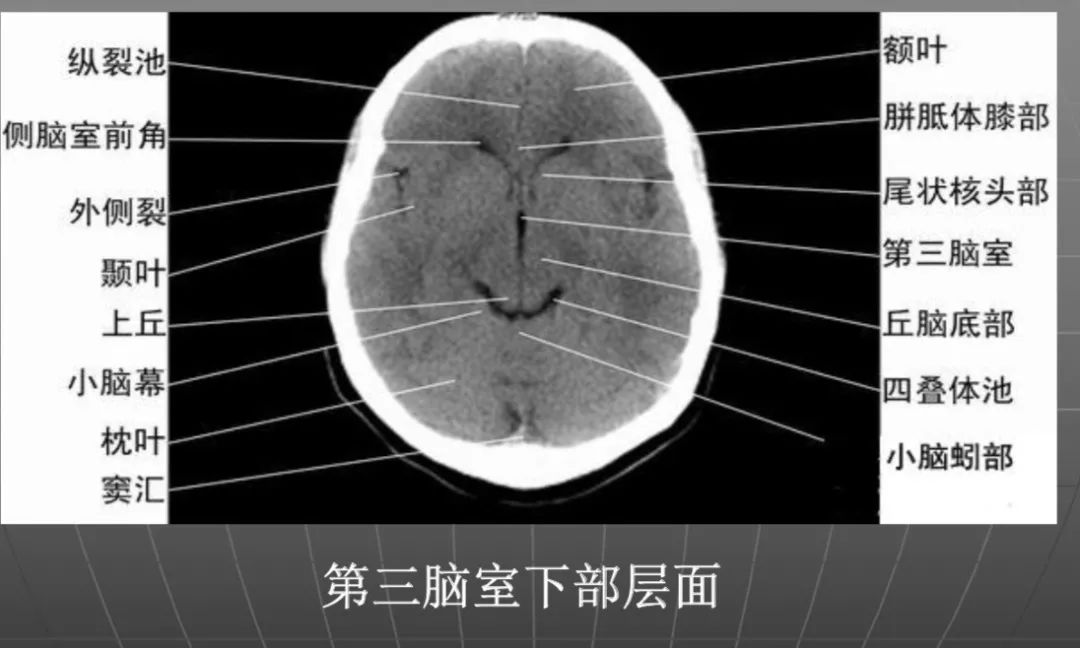

3、第三脑室下部层面显示侧脑室前角的下部:

前方——额叶;外侧——尾状核头部;后方中线处——第三脑室,其两侧连接丘脑。

颅后窝:

“Y”字形或“V”字形的小脑幕,幕下结构在内侧(小脑上蚓部),幕上结构在外侧(枕叶)。

四叠体池:

位于小脑蚓部前方。